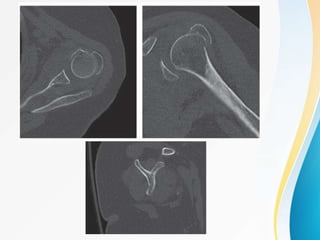

CT Scan :

Allows more detailed understanding of fracture

configuration, degree of osteopenia, presence and location

of bone impaction and extent of fracture comminution.